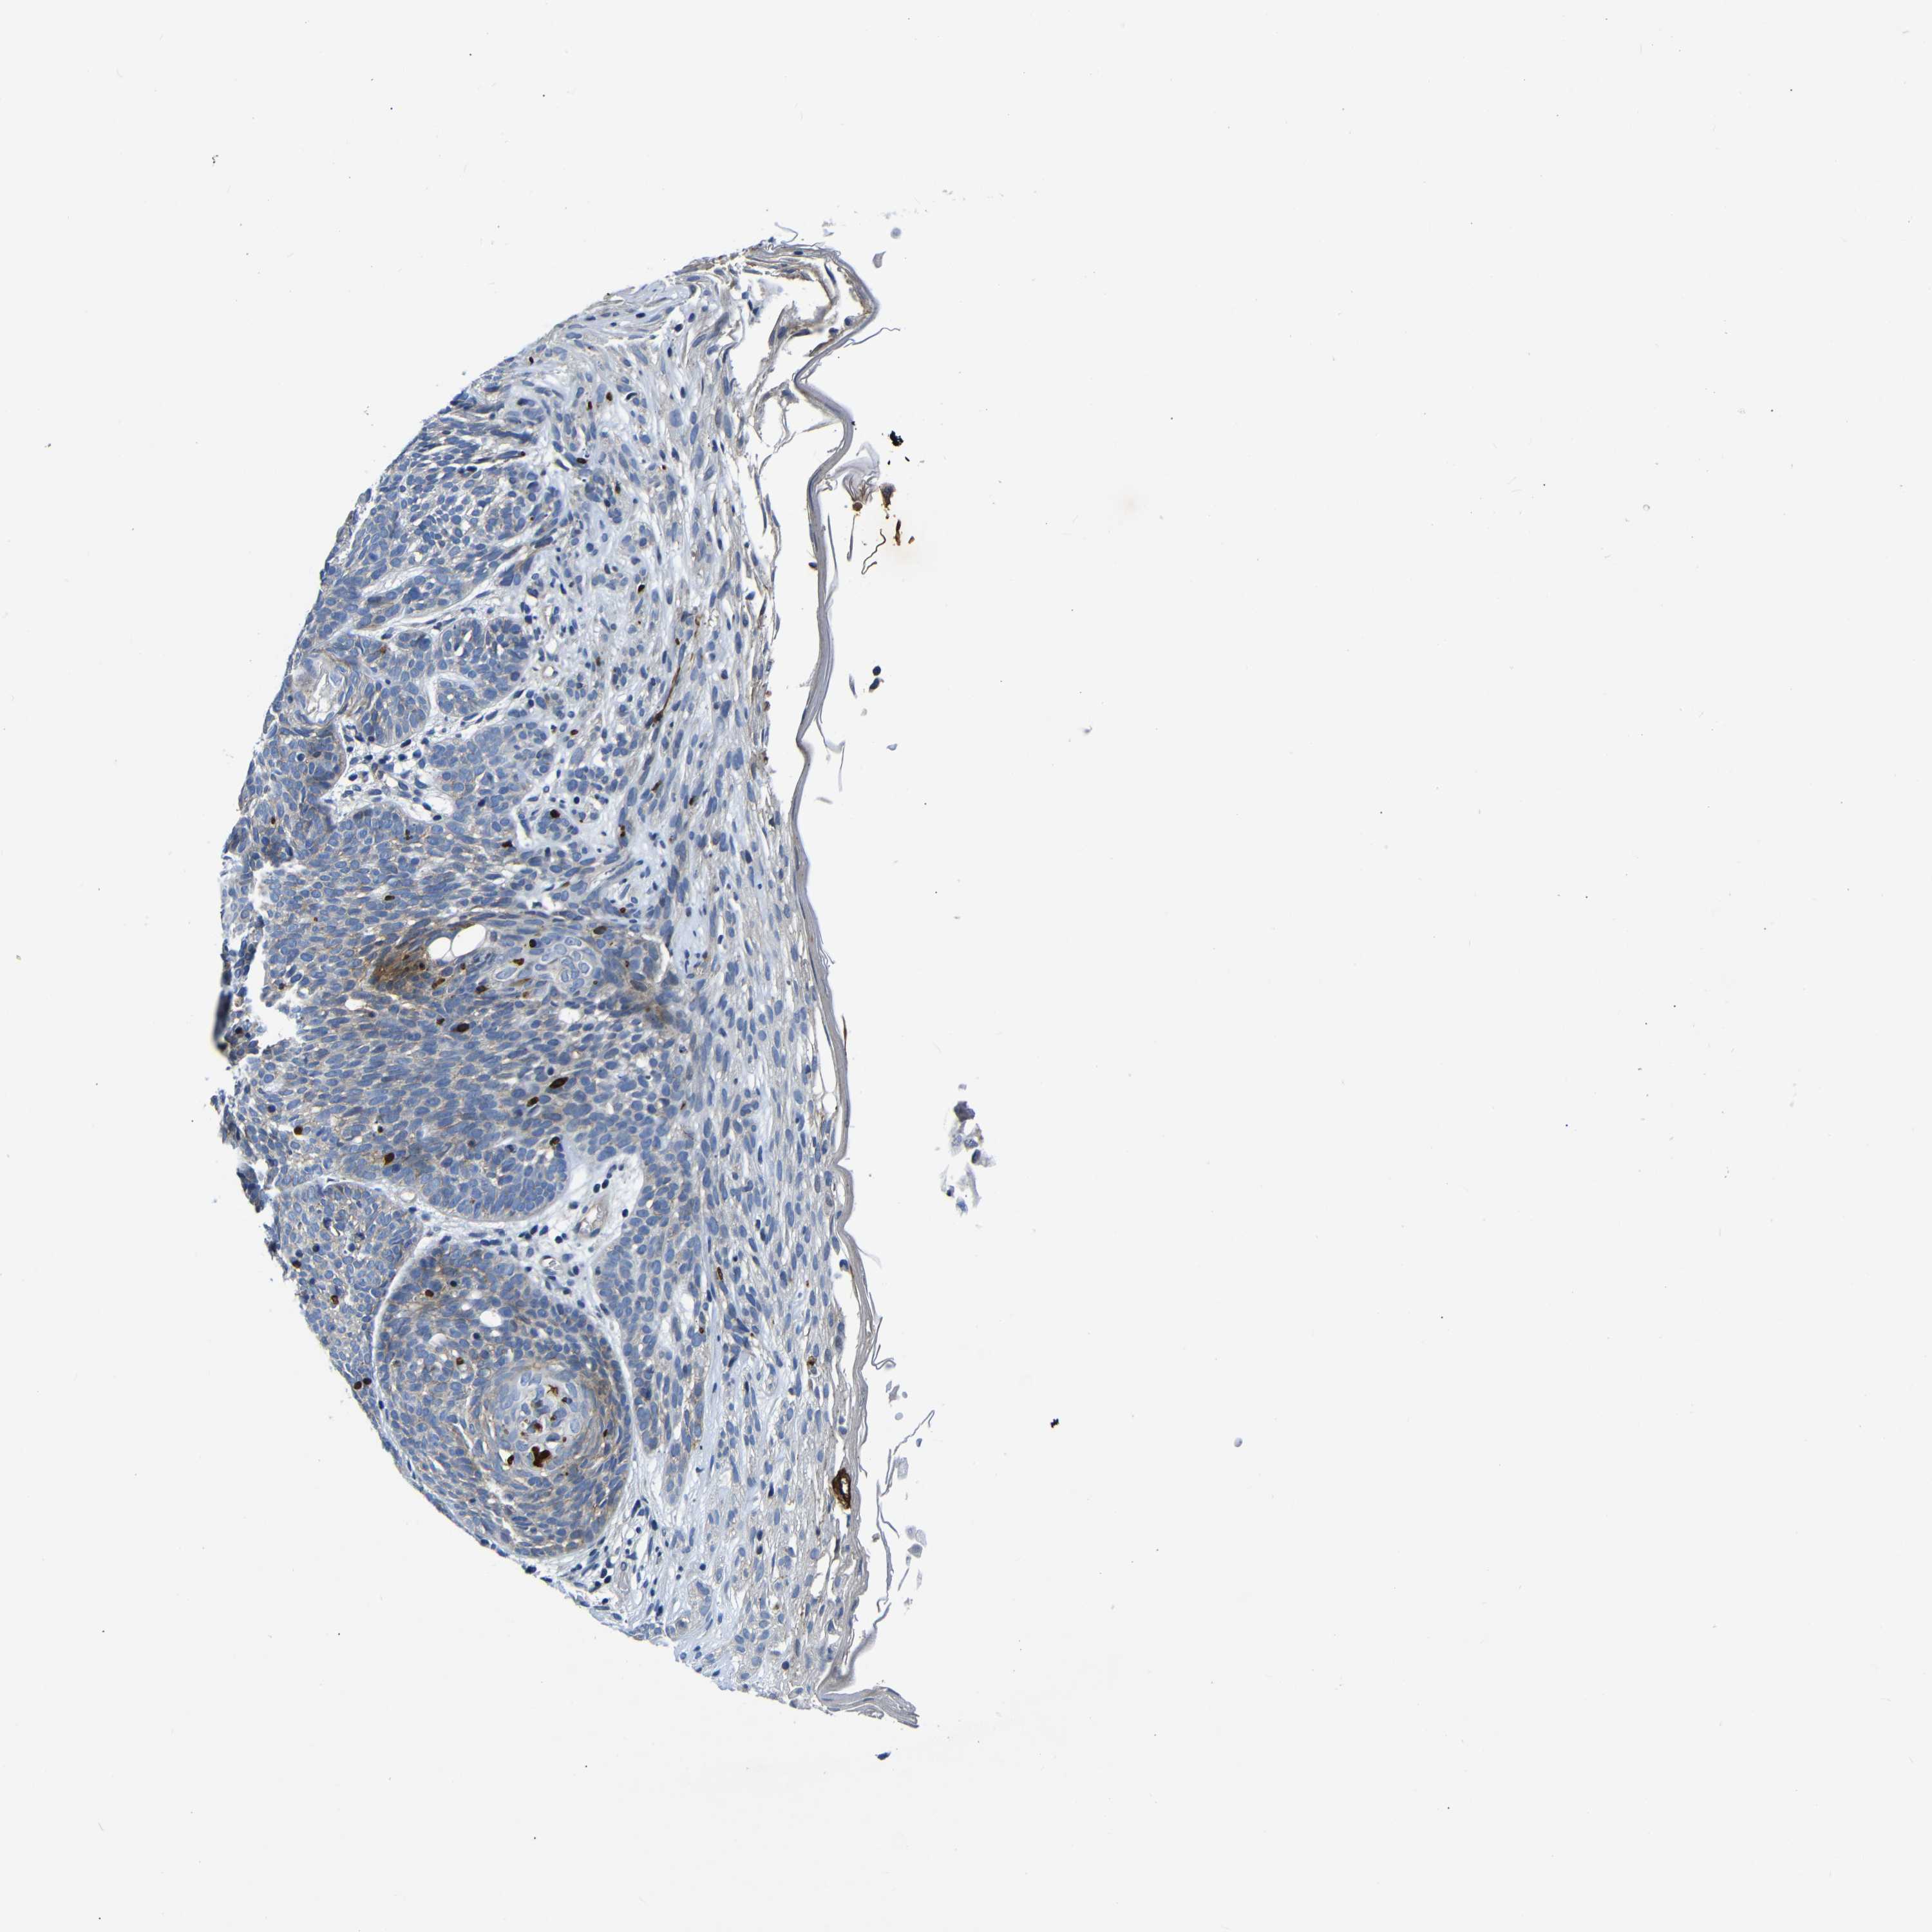

SKIN CANCER - Protein expressioni

A mouse-over function shows sample information and annotation data. Click on an image to view it in a full screen mode. Samples can be filtered based on level of antibody staining by selecting one or several of the following categories: high, medium, low and not detected. The assay and annotation is described here.

Each image is clickable and will lead to virtual microscopy that enables deeper exploration of all samples and also displays staining intensity scores, fraction scores and subcellular localization as well as patient and tissue information for each sample.

HPA030212

HPA030213

HPA030214

HPA030215

CAB013496

Staining

High

Medium

Low

Not detected

Intensity

Strong

Moderate

Weak

Negative

Quantity

>75%

75%-25%

<25%

None

Location

Nuclear

Cytoplasmic/membranous

Cytoplasmic/membranous,nuclear

Basal cell carcinoma

Squamous cell carcinoma, NOS

Squamous cell carcinoma, metastatic, NOS

Adnexal tumor, benign